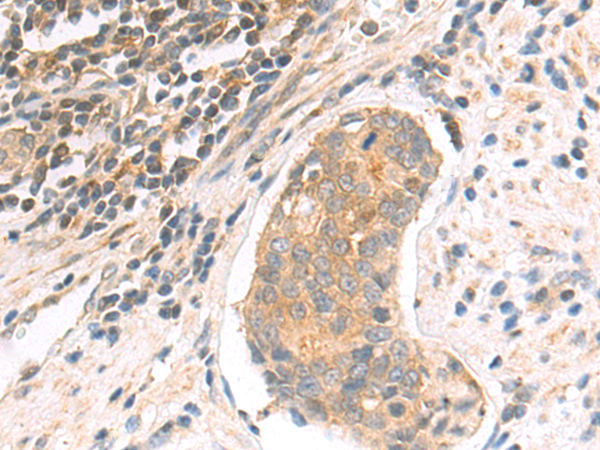

IHC positive control:

Human lymphoma and human breast cancer

IHC Recommend dilution:

10-50